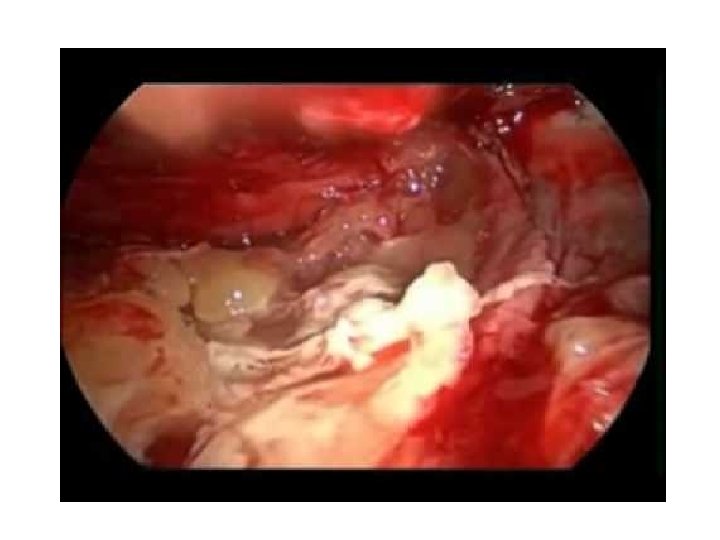

VATS vs. Intrapleural Fibrinolytics UT Southwestern Study Patients (20) with pleural infection who were suitable for general anesthesia were randomized to receive either immediate VATS or chest tube insertion with additional instillation of intrapleural streptokinase for 3 days. The surgical group had higher primary treatment success (10/11 patients) and all streptokinase medical failures (5/9 patients) were salvaged by surgery without requiring thoracotomy. Surgical patients also had a shorter drainage period (5. 8 vs. 9. 8 days), hospital stay (8. 7 vs. 12. 8 days), and cost savings. Wait MA, Sharma S, Hohn J, et al. A randomized trial of empyema therapy. Chest 1997; 111: 1548 e 51. (1 L).

Empyema Surgery Drainage of fluid and pus – free up the pleural space Decortication – free up the trapped lung, re-expansion, obliterate any residual pleural space Chest tube Insertions – post-operative drainage